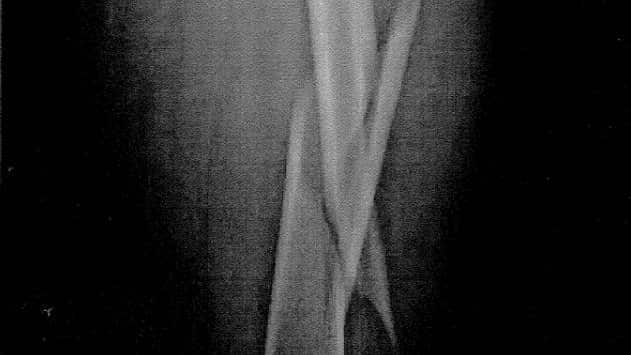

X光片顯示哥斯利事發後左腿骨折。 Source: Courts Administration Authority

澳洲廣播公司(ABC)報道,南澳警員於2013年3月在阿市中心Bank St追捕男子哥斯利(Matthew Charles Crossley)時,先使用了胡椒噴霧,隨後以一招格鬥式「四型鎖腿」(figure four leg lock)將其制服。法庭聆悉,該招「鎖腿技」可以限制對手掙扎,結果導致哥斯利的股骨嚴重骨折。他隨即要接受手術,植入了40厘米長的固定桿。

法庭聆悉,哥斯利受傷後一年幾乎都要用拐杖輔助行走,之後要持續接受治療。有心理醫生作供稱其患上創傷後壓力症候群(PTSD)。事發後他因「身體不許可」再也沒有工作。